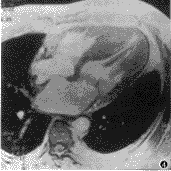

图4、5 非匀称型肥厚型心肌病长轴位电影,图4为舒张期,图5为收缩期,可见二尖瓣前叶向室间隔移动(箭头)

流出道狭窄时四腔位动态电影显示:左室收缩时室间隔轻度增厚,二尖瓣前叶向前移位,室间隔左室面与二尖瓣前叶之间形成一条狭窄通道,并可见由于狭窄和高速射血产生的血流信号丢失导致的“涡流”征象(turbulent flow)(图4、5)。可见由于流出道狭窄、二尖瓣前移造成二尖瓣关闭时对位不良,二尖瓣口在左室收缩期可见二尖瓣轻度返流征象,并见左房轻度扩大。

一般认为左室流出道狭窄是由于左室收缩时高速血流使二尖瓣前叶两面压力差带动二尖瓣前移,进而使流出道变窄。同时,左室收缩时不匀称肥厚的室间隔左室面收缩增厚,局部凸向流出道而加重流出道的狭窄,但前者是主要原因[6]。